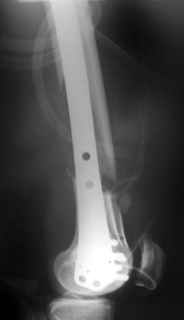

And why LISS is superior here than nail?

Look what we would have done.